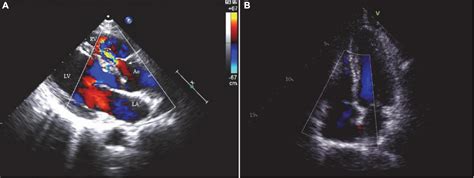

Transesophageal Echocardiography Tomographic Views - Clinical Tree